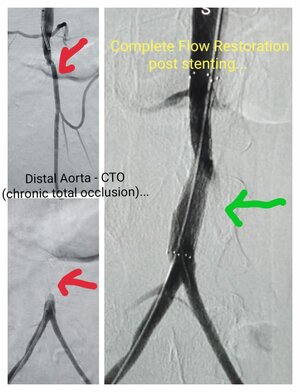

Complete total occlusion ( CTO) in Distal Aorta. Pre Procedure- No blood flow due to complete stenosis & Post Procedure- Deployed Stent & restore complete blood flow